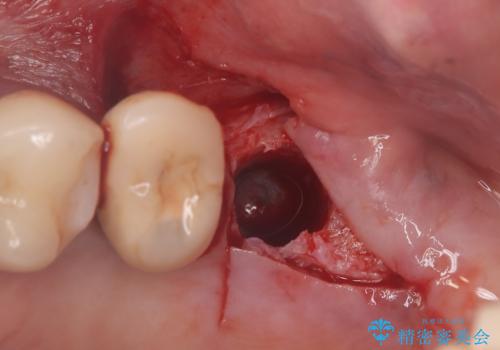

左上6番目の歯が根っこ部分で破折しており、噛むたびに痛みが生じる状態でした。

保存不可能と判断し、抜歯から骨ができるのを3か月待ってインプラント治療を行いました。

歯根破折により抜歯となり、インプラント治療(一回法)にて補綴修復を行いました。

抜歯から3か月程骨ができてくるのを待ってからインプラントを埋入しています。

埋入時には上顎洞粘膜を数ミリ挙上しています。